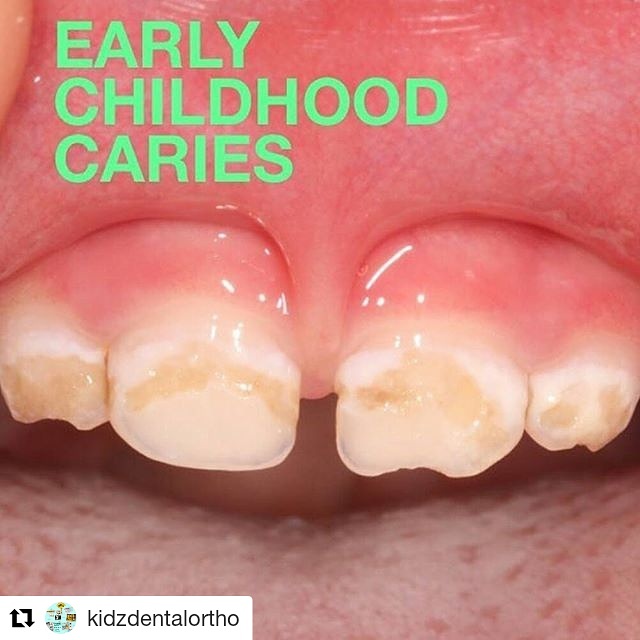

Karies Gigi Pada Balita - Kidz Dental Care

Karies Gigi Pada Balita - Kidz Dental Care

Karies Gigi Pada Balita - Kidz Dental Care

Karies Gigi Pada Balita - Kidz Dental Care

Karies Gigi Pada Balita - Kidz Dental Care

Karies Gigi Pada Balita - Kidz Dental Care